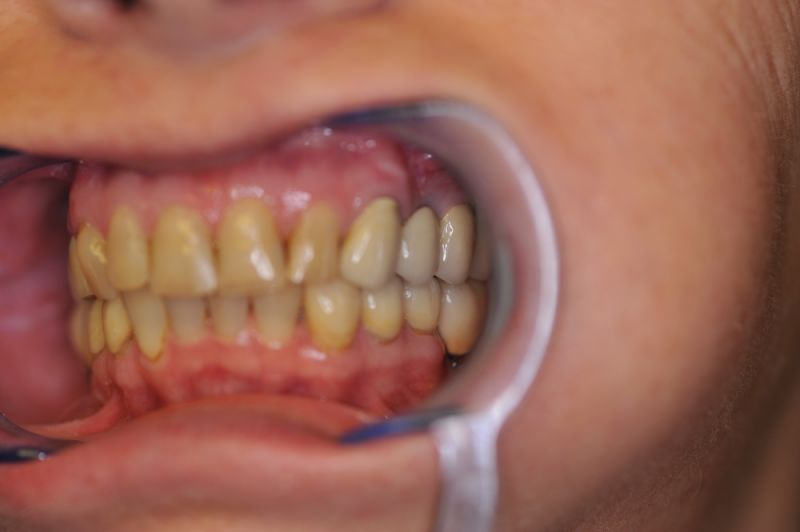

Es war eine Kombination aus Schmerzen bis an die Suizidgrenze, beschränkten wirtschaftlichen Möglichkeiten, sehr stark eingeschränkten Möglichkeiten der für Implantate zur Verfügung stehenden Knochenverhältnisse in einem stark atrophierten Unterkieferseitenzahnbereich und zudem dann auch noch durch auftretenden Problemen bei der Implantatinsertion und nachfolgenden Versorgung der Implantate.

Alle 3 Monate Recall! Das ist jetzt Pflicht für diese Patientin und zwar so lange, so lange sie mit dieser Arbeit durch die Gegend laufen möchte! Und eiserne Disziplin bei der Mundhygiene!